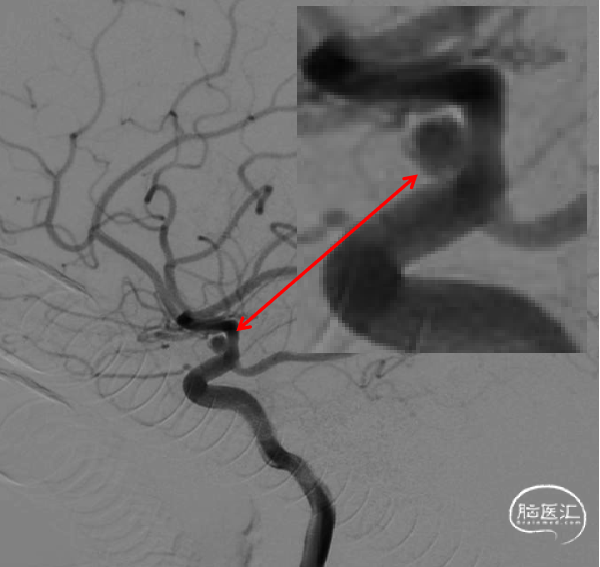

2周复查造影显示:3*3.2mm颈内末端动脉瘤一期采用Atlas支架辅助弹簧圈栓塞术后2周复发,动脉瘤体增大。

复查3D造影显示:3.5mm*4.4mm*3.2mm颈内末端动脉瘤一期采用Atlas支架辅助弹簧圈栓塞术后2周复发,动脉瘤体增大。

3D重建测量:

1)动脉瘤大小6.2*4.7mm

2)FD覆盖长23mm

3)远端血管2.4mm,近端血管3.5mm

动脉瘤的大小在短期内体积迅速增大,证实为血泡样动脉瘤。